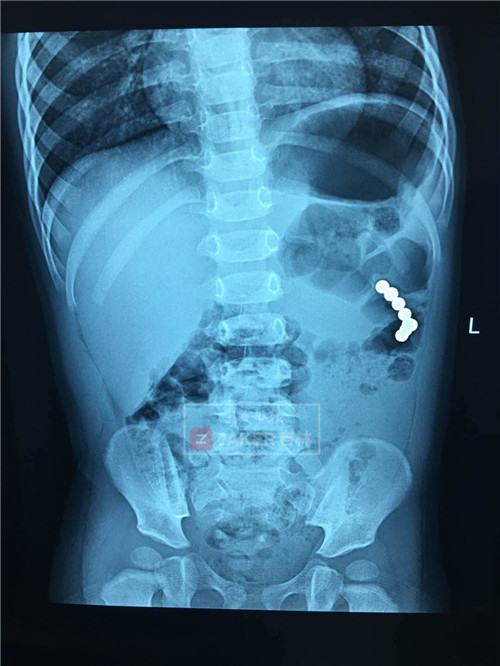

孩子低熱、不愛(ài)吃飯,情緒不好,難道是感冒了?經(jīng)檢查,這些癥狀的主因竟是孩子吞下了 8 枚磁力珠,并且已經(jīng)造成胃腸穿孔。如果不及時(shí)取出,情況很危險(xiǎn),甚至威脅到生命。

門(mén)診接診醫(yī)生張春艷立刻給患者拍片,明確患兒的確吞下磁力珠,數(shù)量在 7-8 個(gè),但是磁力珠的具體位置不明確。

邊鵬說(shuō),當(dāng)日下午 3 點(diǎn)半到 4 點(diǎn),為患者實(shí)施全麻,通過(guò)胃鏡,發(fā)現(xiàn)胃里有 2 個(gè)磁力珠,而其中一個(gè)在胃壁上嵌著,已經(jīng)穿孔。

耿輝主任介紹,術(shù)中發(fā)現(xiàn),患者兩次吃進(jìn)磁力珠,第一次吃的磁力珠已經(jīng)到結(jié)腸位置,后吃進(jìn)的磁力珠在胃內(nèi)。兩個(gè)位置的磁力珠粘附,把胃壁和結(jié)腸壁吸在一起,吸力太大,導(dǎo)致胃粘膜和腸粘膜缺血、壞死,造成胃穿孔、結(jié)腸穿孔。